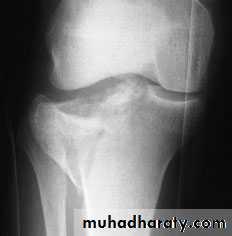

TIBIAL PLATEAU FRACTURES

Mechanism of injuryFractures of the tibial plateau are caused by a varus or valgus force combined with axial loading (a pure valgus force is more likely to rupture the ligaments).This is sometimes the result of a car striking a pedestrian(hence th e term ‘bumper fracture’); more oftenit is due to a fall from a height in which the knee is forced into valgus or varus. The tibial condyle iscrushed or split by the opposing femoral condyle,which remains intact.

Schatzker classification of Tibial Plataue Fracture

Type 1 – a vertical split of the lateral condyle.Type 2 – a vertical split of the lateral condyle combined with depression of an adjacent loadbearing part of the condyle.

Type 3 – depression of the articular surface with an intact condylar rim.

Type 4 – fracture of the medial tibial condyle.

Type 5 – fracture of both condyles.

Type 6 – combined condylar and subcondylar fractures.

Imaging

Anteroposterior, lateral and oblique x-rays will usually show the fracture, but the amount of comminution or plateau depression may not be appreciated without computer tomography (CT).Treatment